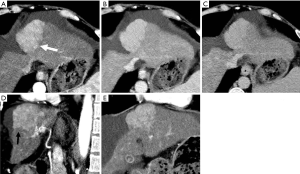

HAPS secondary to HCC may occur through the following routes: (I) transvasal: early invasion and tumor thrombi formation in the branches of the portal vein is frequent in HCC. Since the hypervascular tumor thrombi are supplied by the vasa vasorum of the portal vein wall (21), hepatic arterial flow may drain into the lumen of the portal vein from tumor thrombi (11). These usually manifest as a central and severe HAPS (Figure 5). (II) Transplexal: HCC may sometimes be associated with compromised portal vein flow, and a subsequent HAPS via the transplexal route may be involved (2,16). Arterial blood shunts to the portal venous and hepatic sinusoids via the peribiliary plexus in these cases and usually presents with moderate HAPS (Figure 6). (III) Transsinusoidal: less frequently, retrograde arterial blood shunts into branches of the portal vein via the hepatic sinusoids because of the compromised hepatic venous flow in HCC, which generally constitutes a mild and peripheral HAPS. (IV) Transtumoral: the arterial blood supply to the HCC can be shunted through the tumor venous into peripheral portal veins (10).

Evaluation of HCC with HAPS

HAP results in the heterogeneous enhancement of the hepatic parenchyma. The enhancement of HCC will be significantly reduced in the situation of serious HAPS due to a large amount of contrast medium flowing into the portal vein through the shunt. On the equilibrium phase, the characteristic washout and extension of the tumor can nonetheless be identified accurately. The equilibrium phase is most useful for diagnosis and delineation of HCC as an area of heterogeneous low density (intensity) (Figures 7,8). The presence of HAPS is not necessarily a contraindication to resection, ablative therapies or other liver-directed therapies, and the degree of resection or other therapy can best be determined in the equilibrium phase (22).